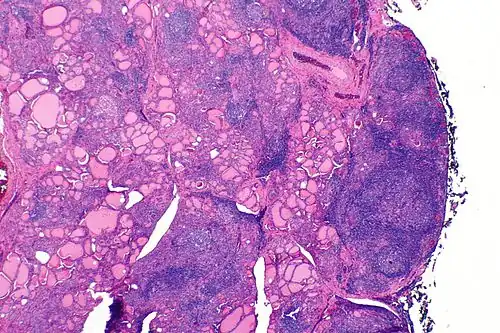

| A micrograph of the thyroid of someone with Hashimoto's thyroiditis | |

Gross morphological changes within the thyroid are seen in the general enlargement, which is far more locally nodular and irregular than more diffuse patterns (such as that of hyperthyroidism). While the capsule is intact and the gland itself is still distinct from surrounding tissue, microscopic examination can provide a more revealing indication of the level of damage.[55] Hypothyroidism is caused by replacement of follicular cells with parenchymatous tissue.[52]

Microscopic examination (histology) will show lymphocytes (including plasma B-cells) diffusely infiltrating the parenchyma.[55] The lymphocytes are predominately T-lymphocytes with a representation of both CD4+ and CD8+ cells.[5] The plasma cells are polyclonal, with present germinal centers resembling the structure of a lymph node[5] (also called secondary lymphoid follicles, not to be confused with the normally present colloid-filled follicles that constitute the thyroid).[55]

In late stages of the disease, the thyroid may be atrophic.[10] Colloid-filled follicles shrink, and the cuboidal cells that usually line the follicles become Hürthle cells.[5] Fibrous tissue may be found throughout the affected thyroid as well.[5] Severe thyroid atrophy presents often with denser fibrotic bands of collagen that remain within the confines of the thyroid capsule.[55]

Generally, pathological findings of the thyroid are related to the amount of remaining thyroid function — the more infiltration and fibrosis, the less likely a patient will have normal thyroid function.[5] A rare but serious complication is thyroid lymphoma, generally the B-cell type, non-Hodgkin lymphoma.[24]